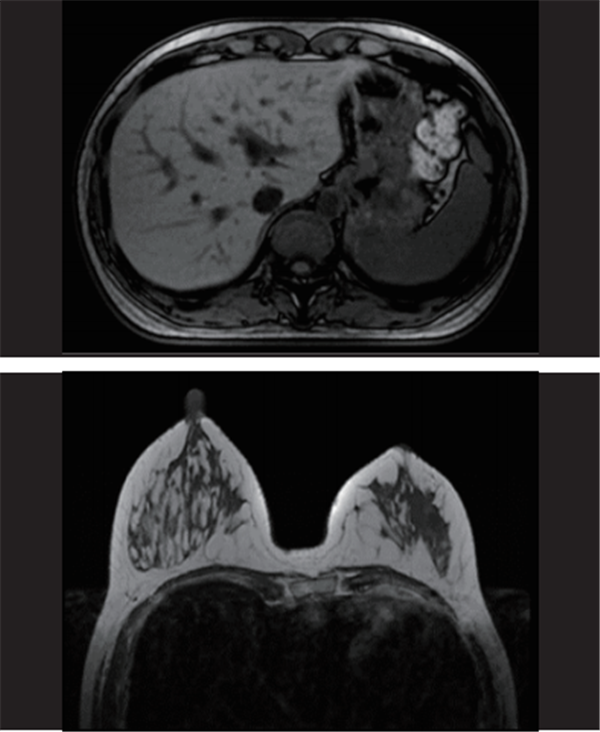

1.5T高场磁共振图像展示

(腹部平扫、乳腺平扫)